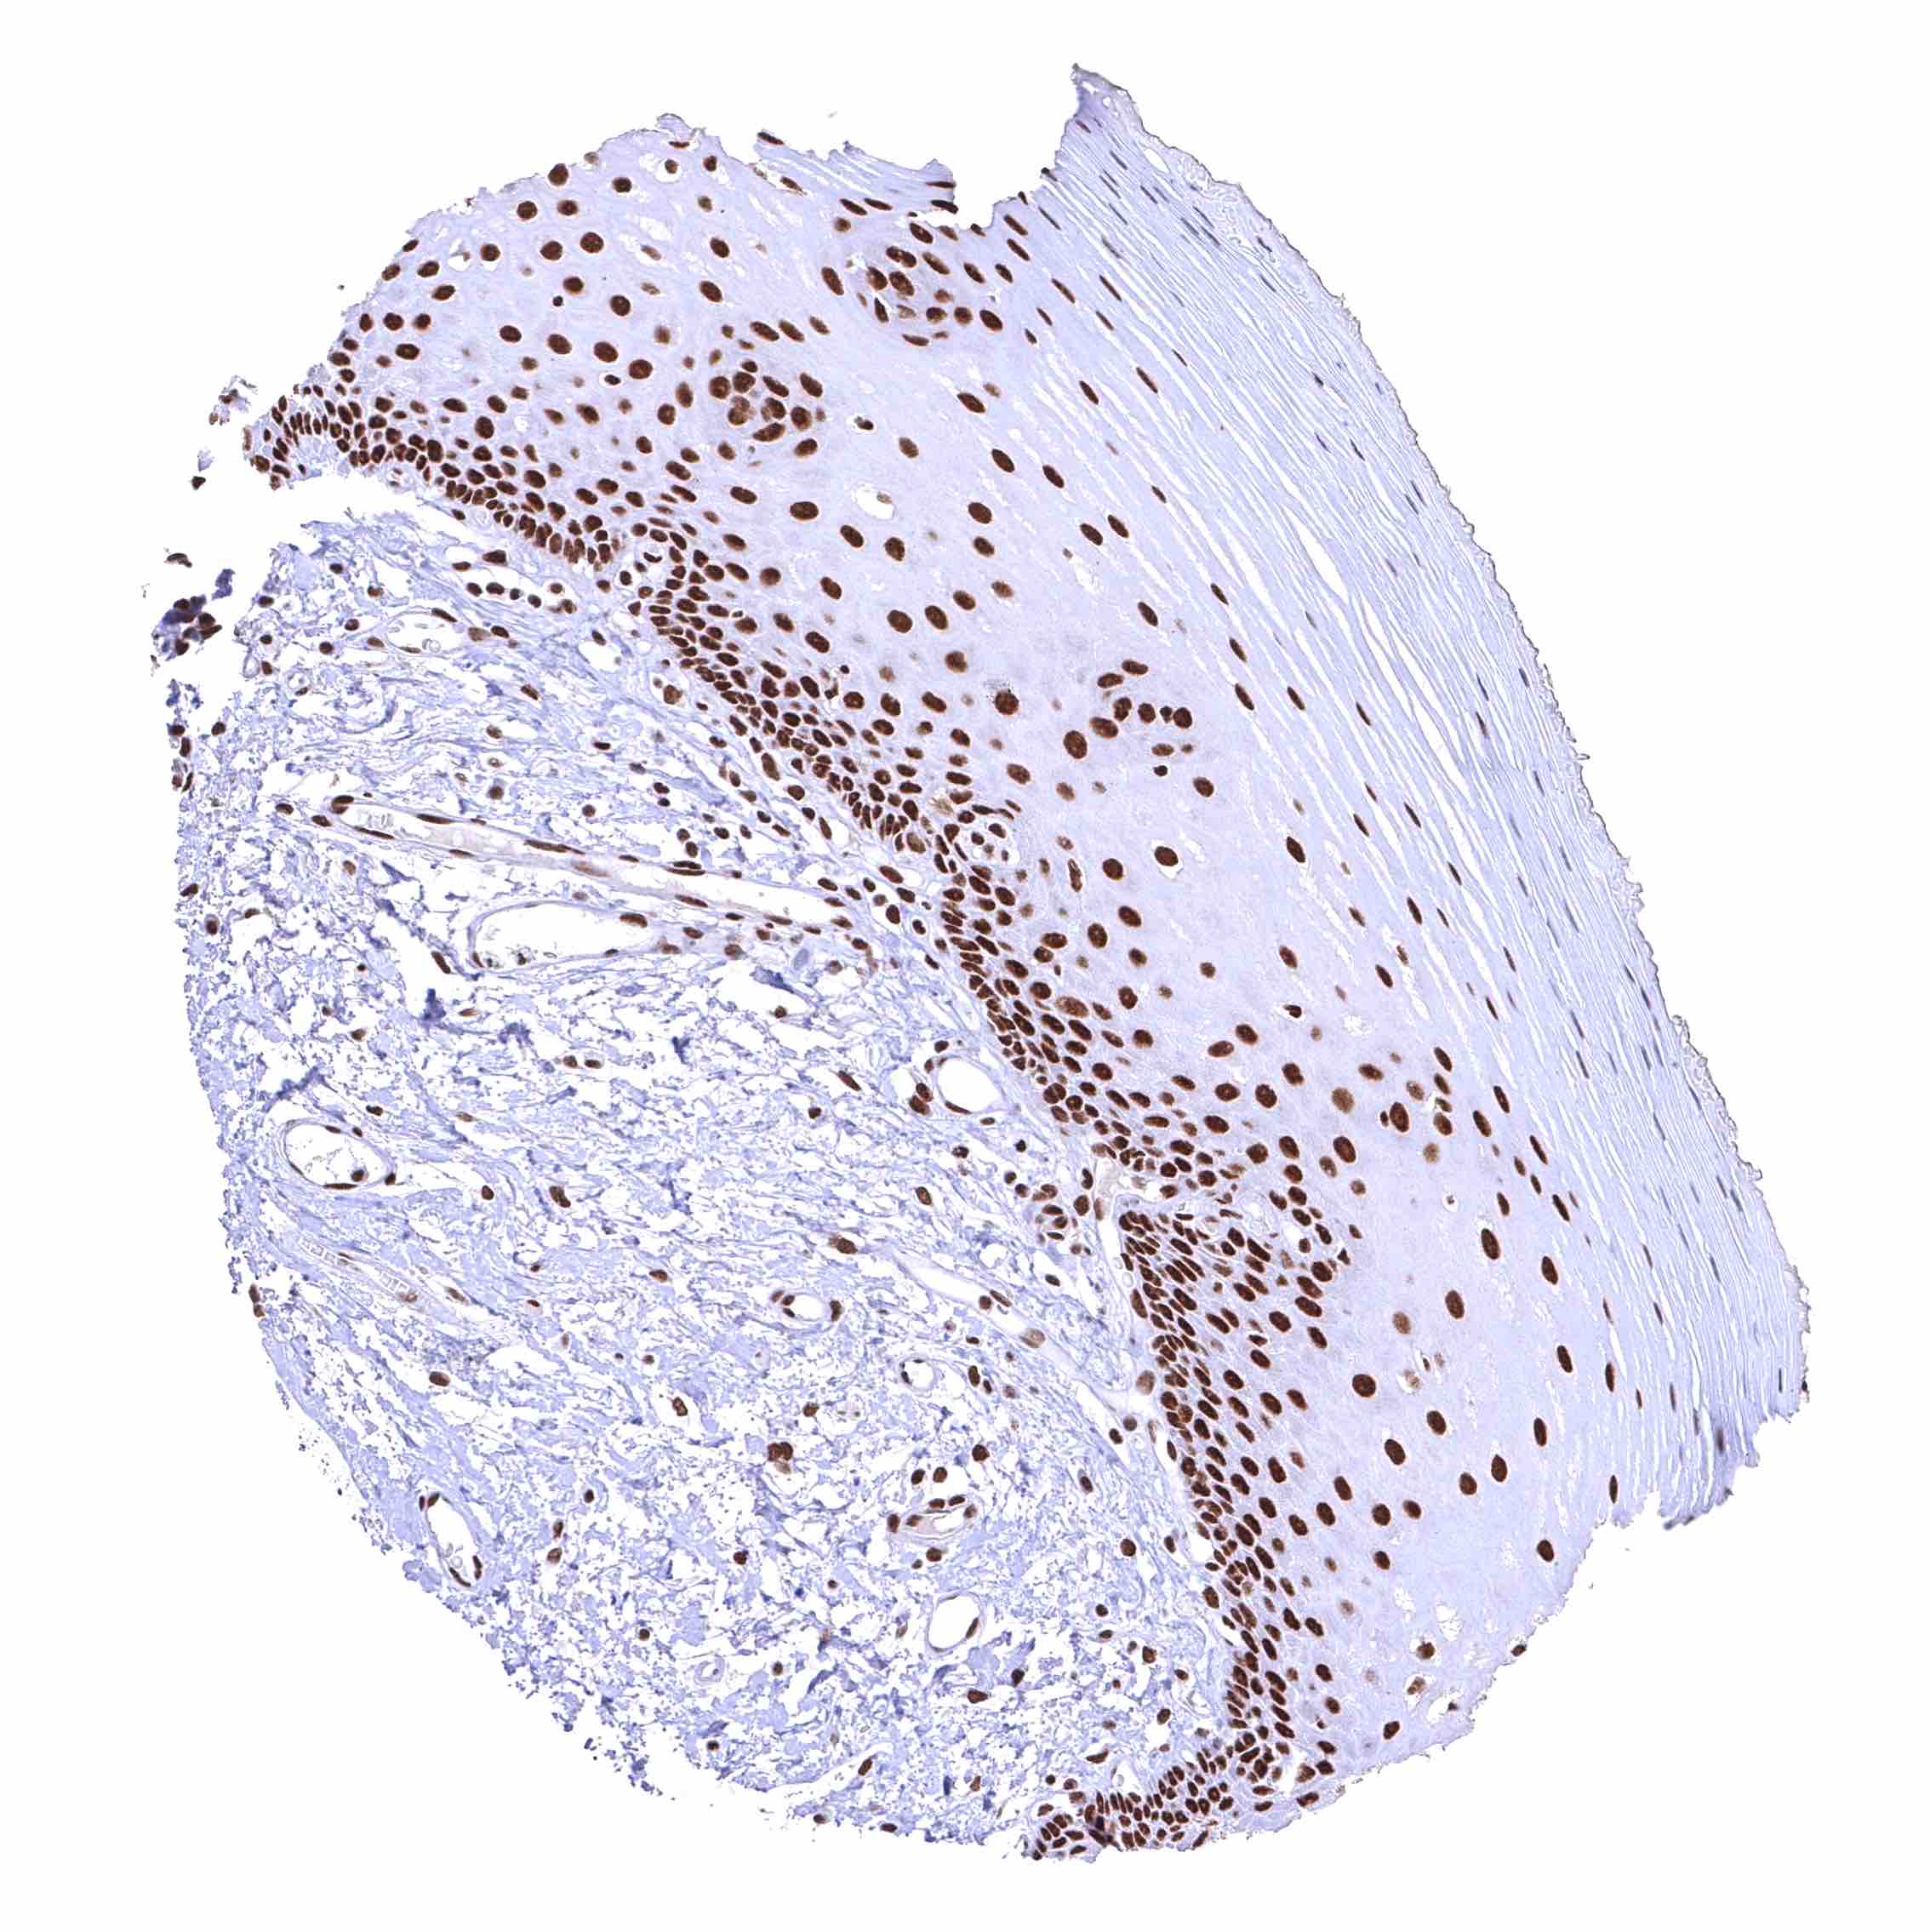

Esophagus, squamous epithelium – Distinct nuclear BRD4 staining of squamous epithelial cells with a slight decrease of the staining intensity towards the most superficial cell layers.

Uterus, ectocervix – Distinct nuclear BRD4 staining of squamous epithelial cells with a slight decrease of the staining intensity towards the most superficial cell layers.